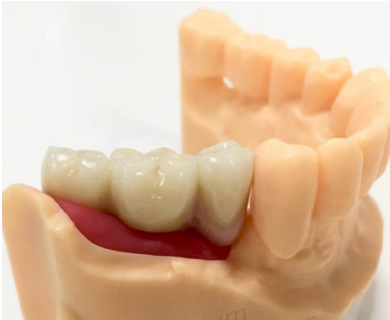

Cinco meses después, se efectuó un nuevo CBCT para evaluar la ganancia ósea conseguida. En el estudio tomográfico pudo observarse una ganancia media vertical de 6,4 mm y una ganancia media horizontal de 7,8 mm, lo que sumado al hueso remanente permitió colocar dos implantes Klockner® KL RP de 4 x 10 mm en 46 y 47 a 35 N/cm2 (Figuras 8-12). El diente 45 se decidió rehabilitar mediante un póntico en extensión para prevenir la lesión del nervio mentoniano durante la inserción de los implantes. La segunda fase se realizó a los tres meses de su colocación. Tras la cicatrización del tejido blando, se tomaron las impresiones mediante el escáner intraoral Carestream Dental CS 3600 y se realizaron las restauraciones protésicas finales con tecnología CAD/CAM (Figuras 13 y 14).